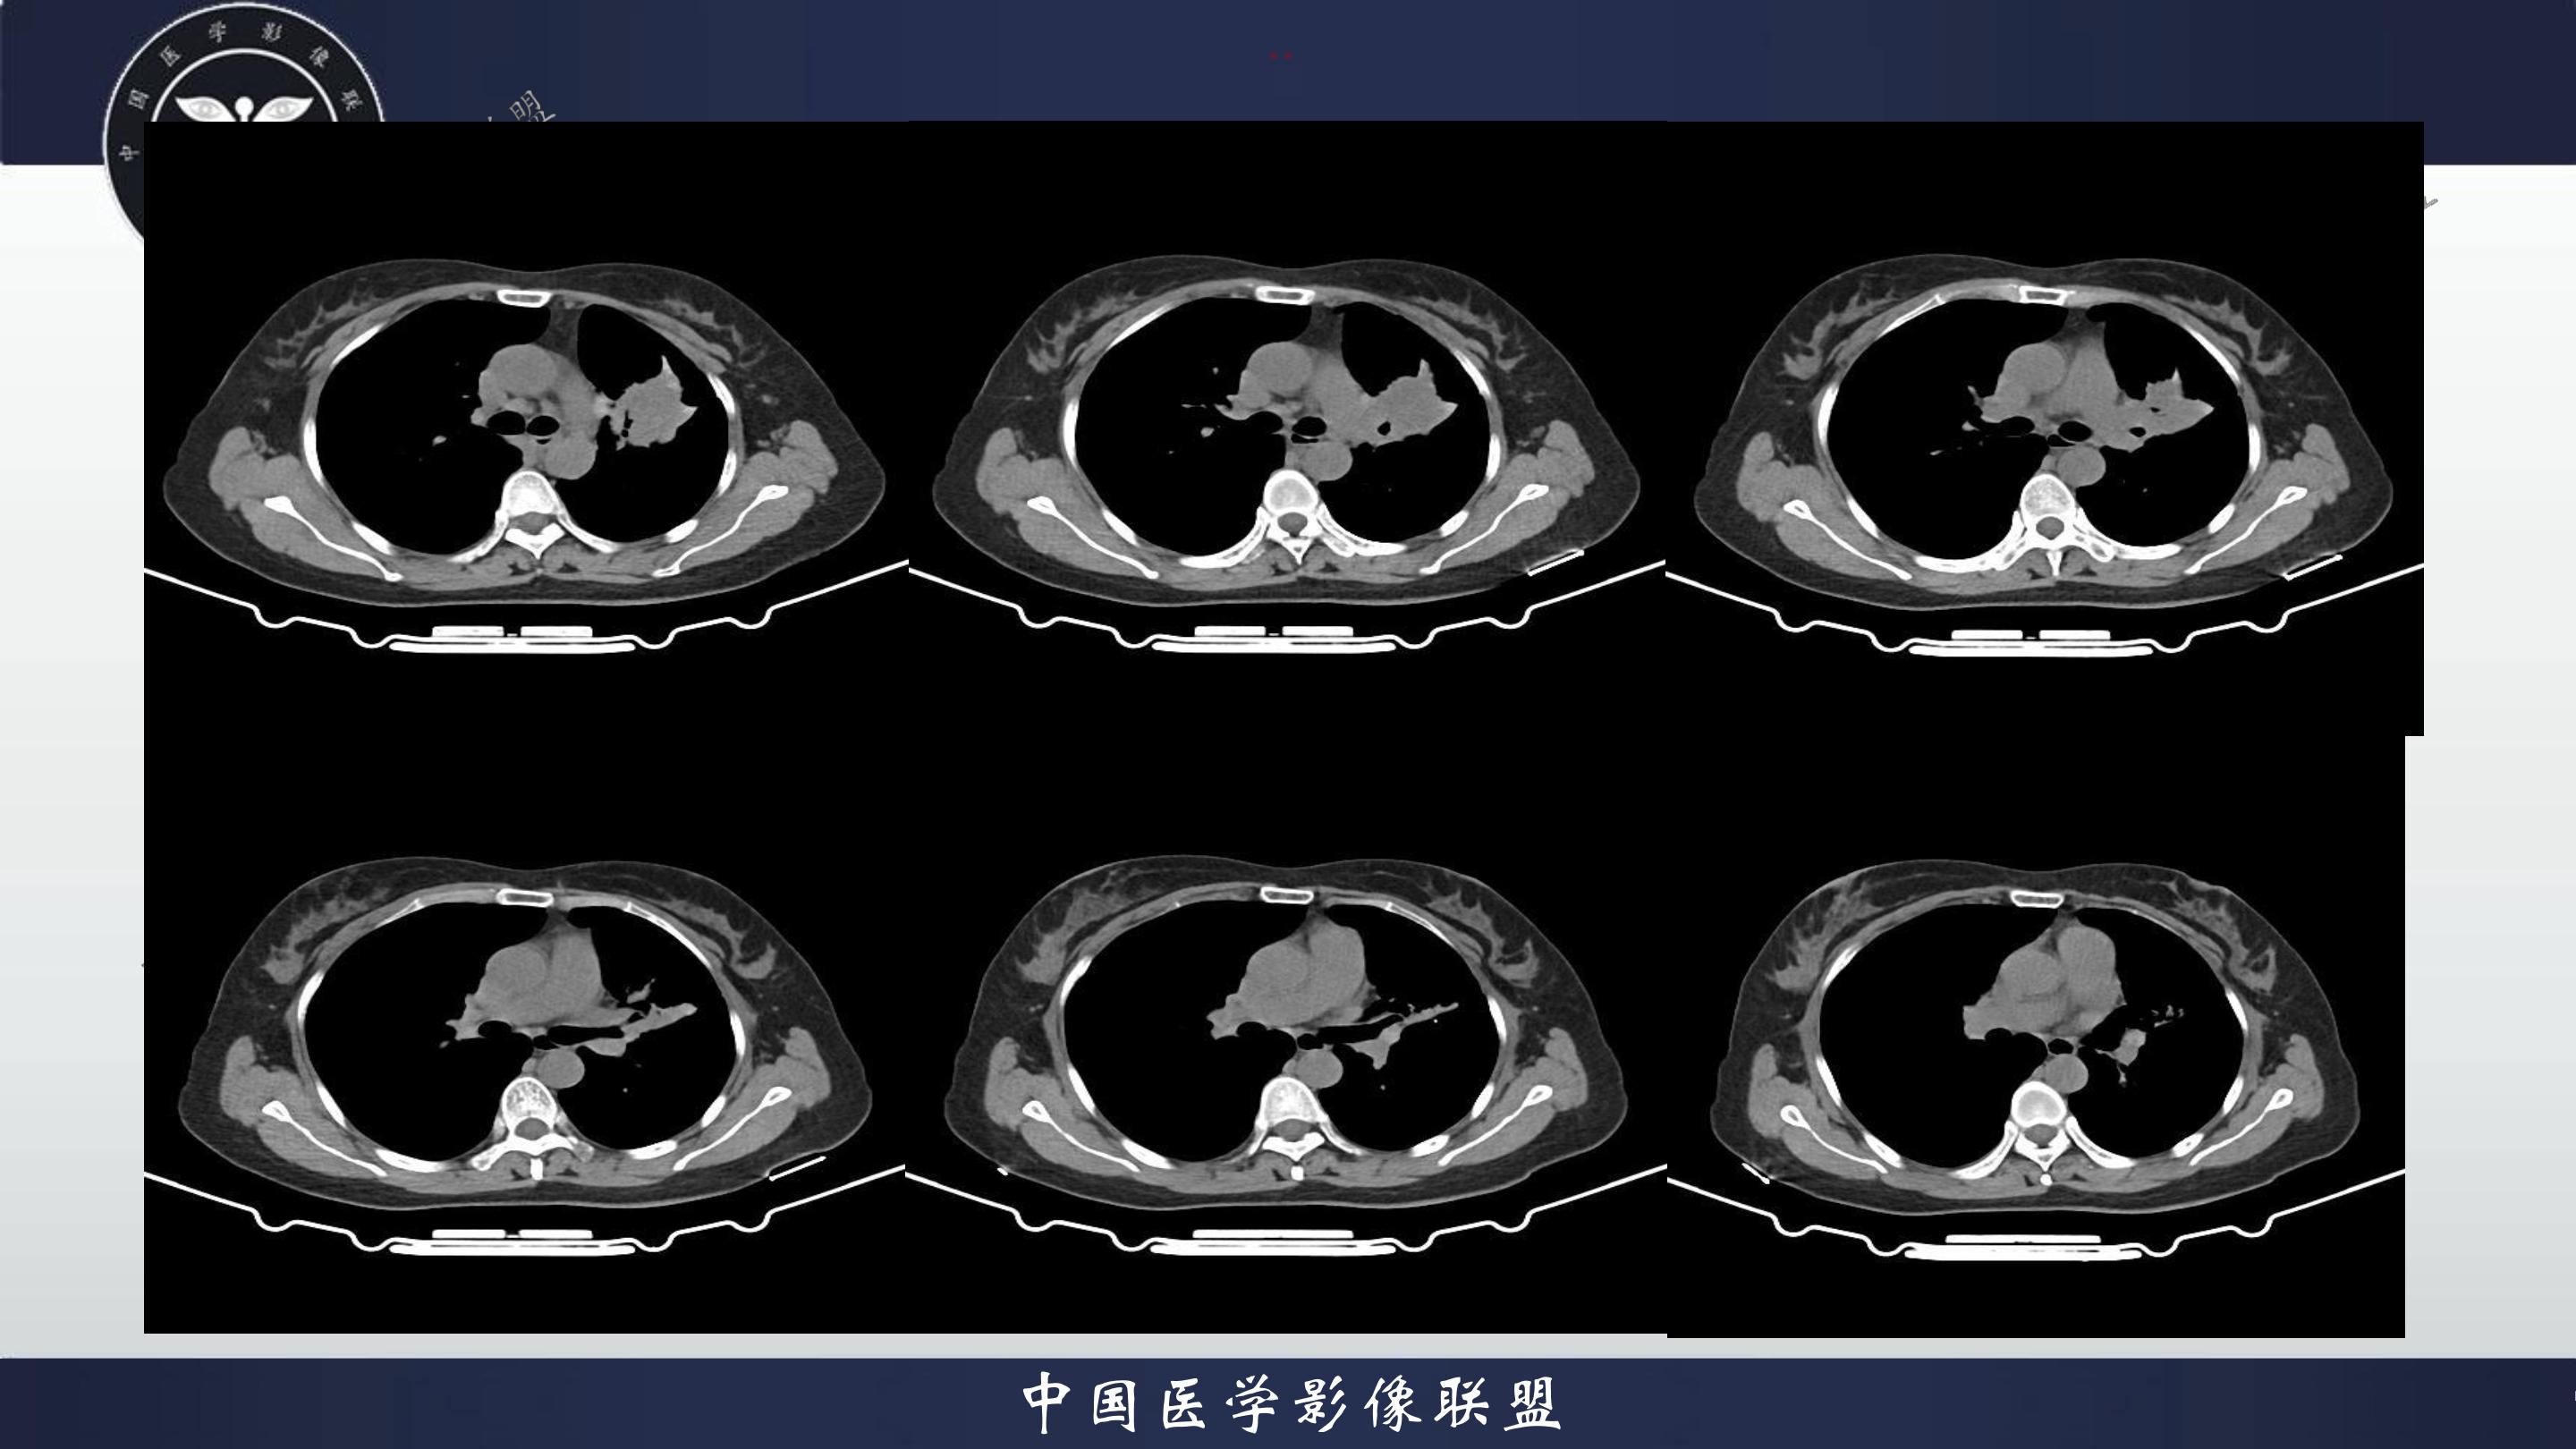

老年女性,咳嗽、咳痰伴痰中带血3月

3月前患者无明显诱因出现咳嗽、咳痰,呈阵发性咳嗽,咳大量黄色脓痰,痰不易咳出,伴痰中带血,量少,具体量不详,伴鼻塞、口干、乏力,活动后感喘息、劳累,休息后缓解,无发热、畏寒,无盗汗,无心慌、胸闷,无腹痛、恶心、呕吐,无头昏、心前区压榨性不适,院外予以输液及口服药物治疗后症状无明显缓解,现为系统诊治就诊我院门诊,门诊以“社区获得性肺炎”收入我科。病来精神、饮食、睡眠尚可,大小便正常,体重无明显变化。

既往有高血压病史10+年,血压最高160/70mmhg,自诉长期口服降压药物治疗,具体药物名称不详;8+年前患者有胆囊结石病史,自诉当时予以手术治疗后好转出院,具体不详;否认“糖尿病、冠心病"等疾病史。否认“肝炎、伤寒、结核”等传染病史;否认已知药物及食物过敏史,否认烟酒史

查体:T:36.8℃P:82次/分,R:20次/分,BP:135/82mmHg,spo2:96%.神清合作,咽稍充血,双侧扁桃体无肿大;双肺呼吸音粗,双肺可闻及少许湿性啰音,未闻及哮鸣音;心界不大,心率82次/分,律齐,心音低钝,各瓣膜听诊区未闻及杂音,腹软,中上腹压痛,无反跳痛及肌卫,肝脾未扪及。双下肢无水肿。

4.辅查:生化报告(2024-11-14 13:06:51)尿素氮或尿素:10.1mmol/L↑,尿酸:342umol/L↑,钾离子:3.16mmol/l↓,尿常规报告(2024-11-14 13:11:41)隐血:+2,凝血报告(2024-11-14 13:16:37)血浆D-二聚体测定:0.62ng/mL↑,生化报告单(2024-11-14 16:14:45)MP滴度(1:40):弱阳性,PCR报告(2024-11-14 16:50:37)人鼻病毒核酸(HRV-RNA)定性:阳性,传染性指标、粪便常规、BNP、心肌特异蛋白、CEA、肝功能、血脂、红细胞沉降率未见明显异常。血气分析回示:PH 7.443 PCO2 28.3mmhg PO2 90.9mmhg HCO3- 19.53mmol/L 氧和指数432.9mmhg;心电图回示:1.窦性心律2.T波改变(Ⅲ倒置、aVF低平)